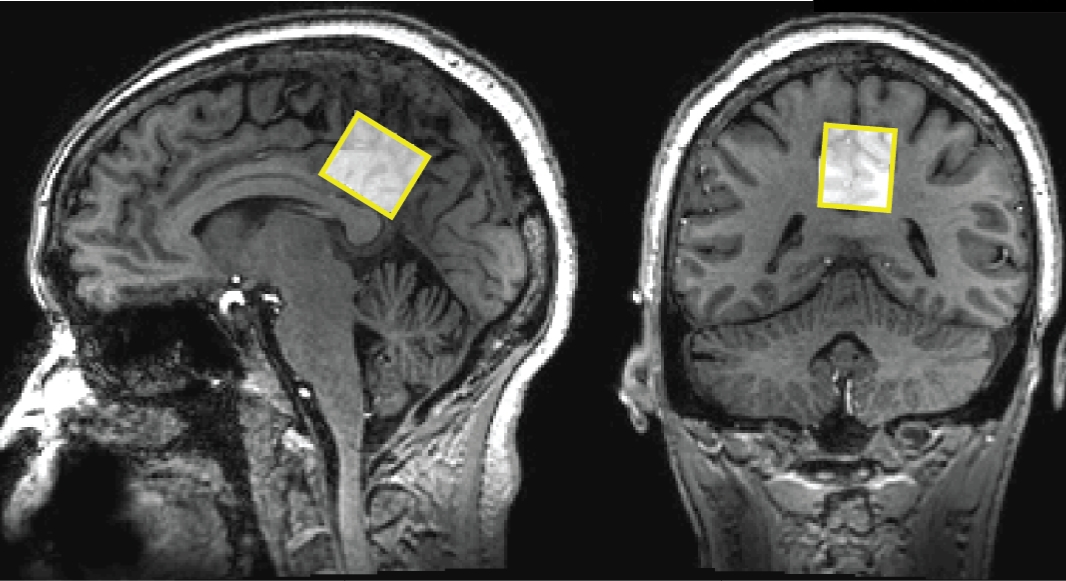

But Dr. Campbell's neuroimaging research, published in the Journal of Neuroscience, revealed something extraordinary: in 87% of tinnitus cases, the ears are functioning perfectly.

The real problem? Brain inflammation has damaged the neural cells that form the "bridge" between your inner ear and your brain's auditory processing center.

"When those brain cells die or get damaged, your brain can't properly interpret the signals from your ear," explains Dr. Campbell. "It fills in the gaps with phantom sounds—that's the ringing you hear."

"They claimed my research was irresponsible," Dr. Campbell recalls. "But my data is peer-reviewed and published. The brain scans don't lie. This approach threatens a multi-billion-dollar industry built on managing symptoms rather than curing the underlying problem."

"If you've tried everything and nothing has worked, it's probably because you've been treating your ears when the problem is in your brain cells," says Dr. Campbell. "Watch the presentation. See the brain scans. Understand the science. Then decide if this approach makes sense for you."